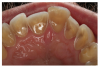

• Constipation from semistarvation, poor nutrient intake, and sometimes-laxative abuse. Additional gastrointestinal findings include delayed gastric emptying, gastric dilation and rupture, dental enamel erosion (Figure 1), palatal trauma, enlarged parotids, inflammation of the esophagus, Mallory Weiss lesions, diminished gag reflex, and elevated transaminases.

• Eventual deterioration of teeth due to frequent vomiting. Poor dental health and loss of bone mass can be lasting signs of the disorder, even if the other physical and mental problems are resolved. Additional oral signs in the disordered state include anemic tissues and chapped lips.